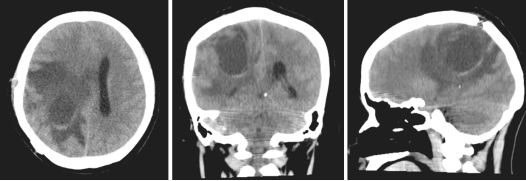

2017年3月26日,患者术后不足3个月,再次因头痛头晕2天入湘雅医院神经外科,行急诊颅脑CT示右侧顶叶囊状新鲜低密度灶,边缘见线样高密度影,周围大片水肿,右侧脑室明显受压变形,中线结构向左偏移,提示局部肿瘤复发,脑疝发生。此时患者胚胎移植后宫内妊娠7+月,患者危重并随时可能发生变化,遂入产科终止妊娠(胎儿胎肺成熟后限期终止妊娠,胎儿状态良好),次日晚突发右侧瞳孔散大,意识障碍,立即予脱水等对症处理后,患者意识恢复。行急诊头颅CT(图4)显示右侧顶叶肿瘤复发,瘤周水肿明显,中线移位。立即入手术室全麻同台行剖宫产术+显微镜下右侧顶叶复发病灶切除术,术后母子平安。

图4. 第二次手术前急诊CT(2017.3.27)